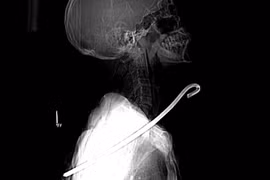

(GLO)- Êkip bác sĩ Bệnh viện Đa khoa tỉnh Hà Tĩnh vừa cứu sống ông V.C.Đ. (SN 1956, trú xã Kỳ Tiến, huyện Kỳ Anh, tỉnh Hà Tĩnh) bị cây sắt dài khoảng 30 cm đâm xuyên cổ.